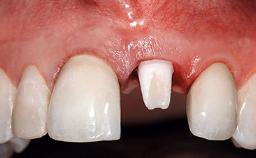

A 32-year-old female Caucasian patient with a compromised maxillary right central incisor was referred to us by a general dentist. Her chief complaints were discomfort and mobility of tooth 11 with unsatisfactory esthetics due to discoloration. The patient reported a previous trauma, some years earlier, as the origin of pathology on the afflicted tooth. Anamnesis was negative for any other dental or periodontal pathology in the remaining dentition. The patient did not take any medication and reported to be a light smoker (5–10 cigs/day). She had high esthetic expectations of her treatment. The extraoral examination revealed a high smile line with full exposure of her maxillary teeth and surrounding soft tissue in the area between the second premolars.

Patient's Esthetic Expectations Low Medium High

Lip Line No exposure of papillae Exposure of papillae Full exposure of mucosa margin

Provisional Implant-Supported Prosthesis Prosthodontic margin > 3 mm apical to mucosal margin Prosthodontic margin > 3 mm apical to mucosal margin

Interim Prosthesis during Healing Fixed Fixed